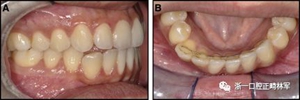

圖18.脫粘后的最終圖像:A,正面視圖; B,咬合面視圖。 進一步的牙齒移動以糾正輕度前牙開合被認為不符合患者的最佳利益。

圖19.A,治療前和B,治療后的三維圖像。注意牙根位置的改善和(右下圖像)右側尖牙面?zhèn)裙琴|的形成。

這一次,病人首選一個可摘保持器。